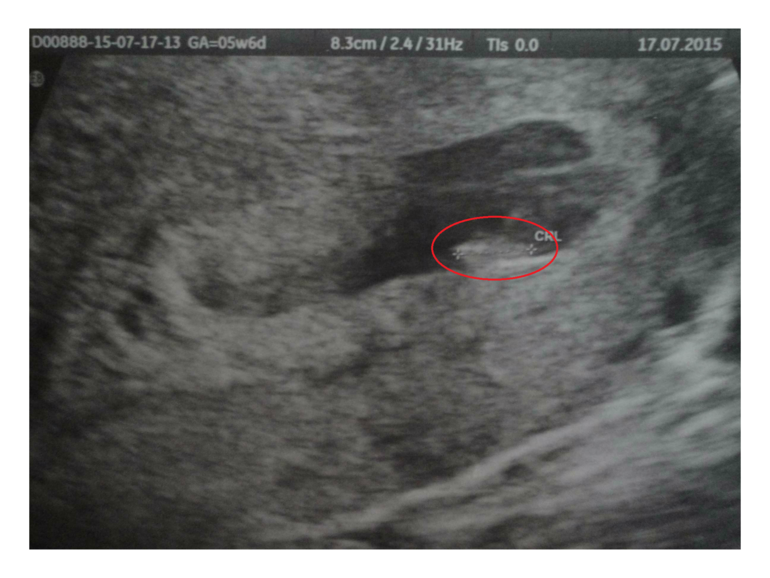

Первое Узи!!! Б 6-7 нед. ПДМ 06/06-2015)

ПЯ 21,5 мм, КТР 6,1 мм, СБ 130 уд/мин!!!